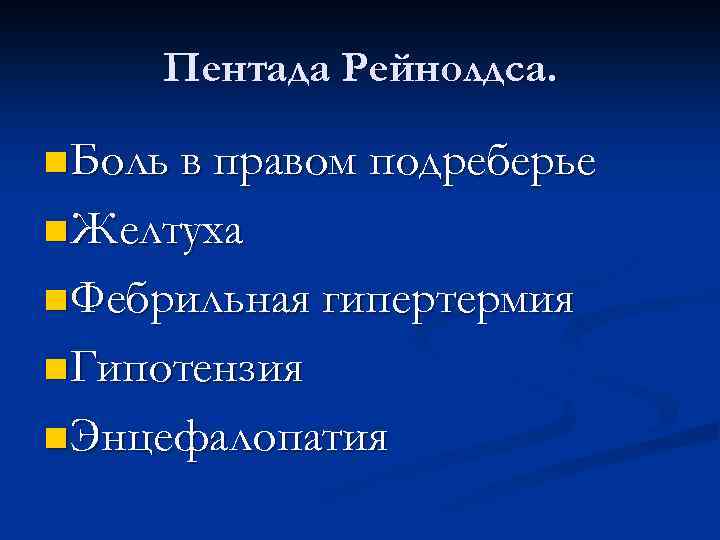

Пентада Рейнолдса. n Боль в правом подреберье n Желтуха n Фебрильная гипертермия n Гипотензия n Энцефалопатия

Пентада Рейнолдса. n Боль в правом подреберье n Желтуха n Фебрильная гипертермия n Гипотензия n Энцефалопатия